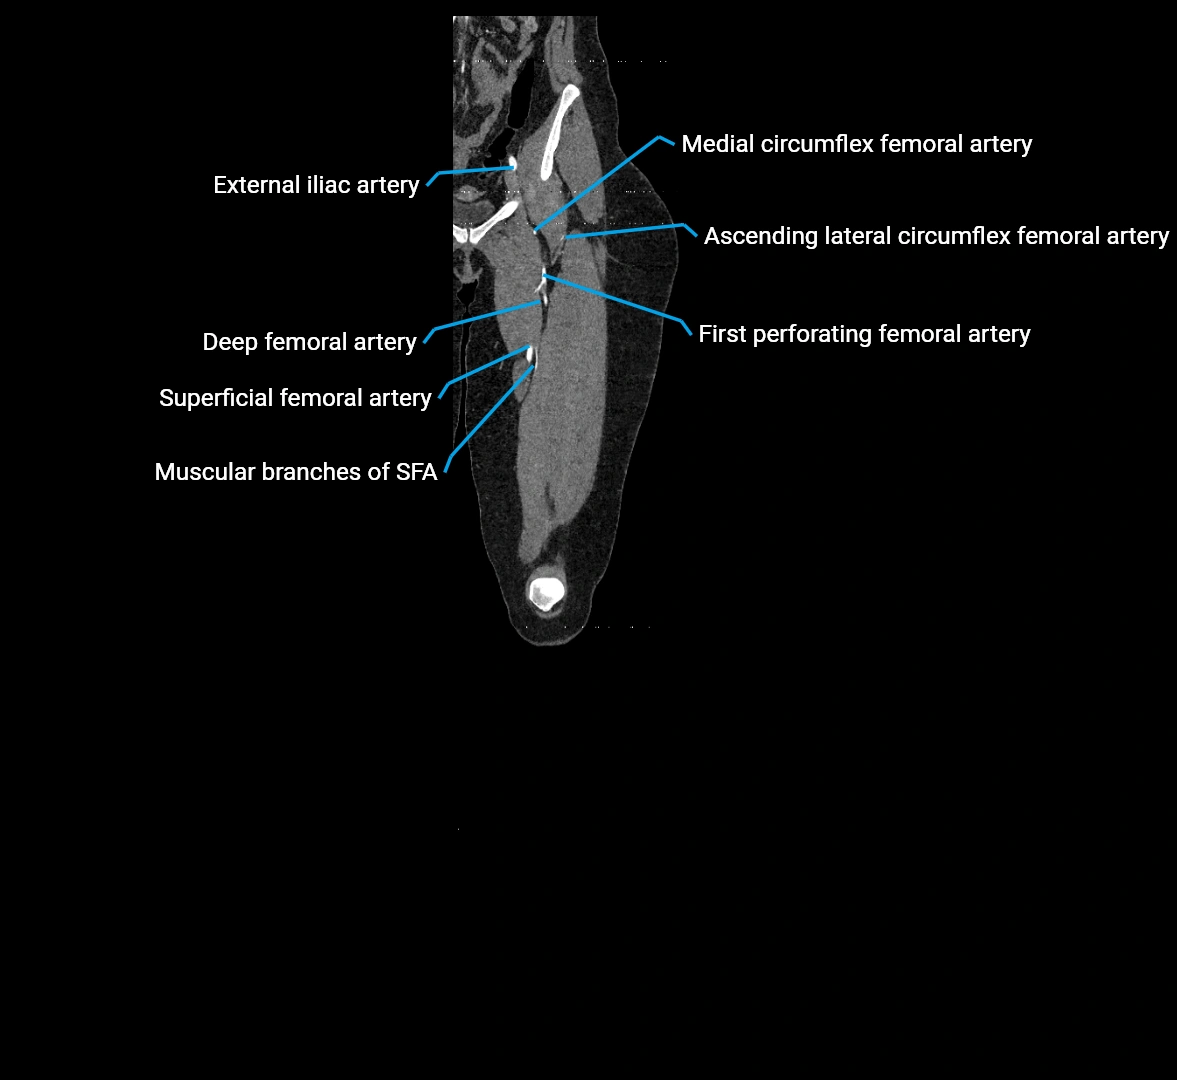

CT images

image

Contrast-enhanced CT (CTA):

• Gold standard for abdominal aortic imaging

• Provides excellent detail of lumen, wall, aneurysm, thrombus, and branch vessels

• Multiplanar and 3D reconstructions help in aneurysm measurement, stent graft planning, and dissection evaluation